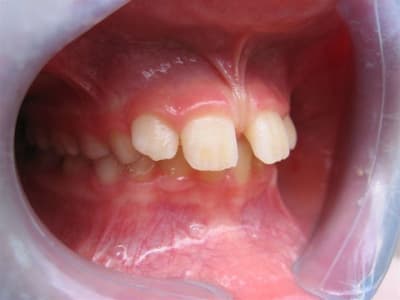

... ma gamine, bientôt 9 ans.

Père CD ... traitement d'ortho.

Mère CD ... traitement d'ortho.

Les conseils sont les bienvenus.

... je vous rassure, le reste de la gamine est lui plutôt réussit.

... pas de rapport avec Tchernobyl ... enfin j'espère!

pour ta gamine je ne suis pas spécialiste mais il me semble que la première chose à faire est une freinectomie,suivie d'un apparei pour corriger l'occlusion

C’est un cas simple ou il faut juste stimuler un peu la croissance et reformer les arcades.

C’est le type même du traitement d’interception en denture mixte.

Pas de panique, petite DDM, bonne classe 2 sq,un peu de supracclusion ---> la laisser grandir un peu, et la confier à un ODF pour un peu de fonctionnelle et un alignement.

... elle est en classe I, avec une grosse supra.

TT "fonctionnel" prévu dans qqs semaines.

... c'est en cours ... un appareil de chez Rocky Mountain va être mis en place, à porter environ 16 heures/jour; il va falloir que je m'en fasse expliquer le principe lors de la séance de pose.